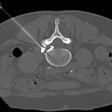

BAE leads to weight loss in pilot study

March 8, 2023